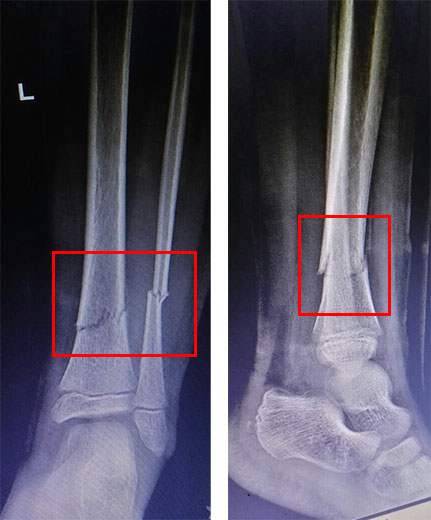

治疗一个月后复查: